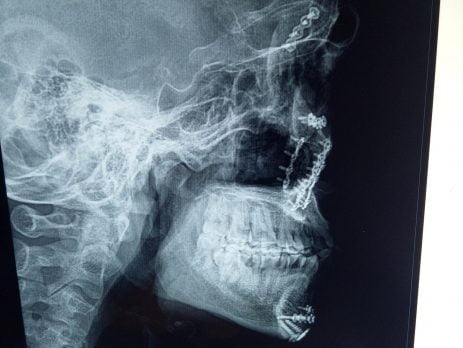

Phẫu thuật thành công số lượng lớn Nep+Vít vùng hàm mặt tại khoa Răng Hàm Mặt Bệnh Viện Đa Khoa Sơn Tây Hà Nội.

Phẫu thuật thành công số lượng lớn Nep+Vít vùng hàm mặt tại khoa Răng Hàm Mặt Bệnh Viện Đa Khoa Sơn Tây Hà Nội. Gồm có 9 nẹp titan+33 vít. Vừa qua kíp phẫu thuật khoa Răng Hàm Mặt đã phẫu thuật thành công cho...